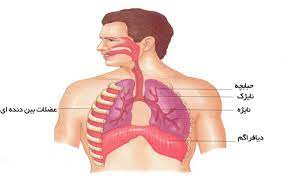

قیمت: 96٬000 تومان - دسته بندی فایل: علوم پزشکیپاورپوینت فیزیولوژی تنفسی (ppt) 123 اسلاید

فروش ویژه پاورپوینت حرفه ای فیزیولوژی تنفسی / تعداد اسلاید: 123 اسلاید